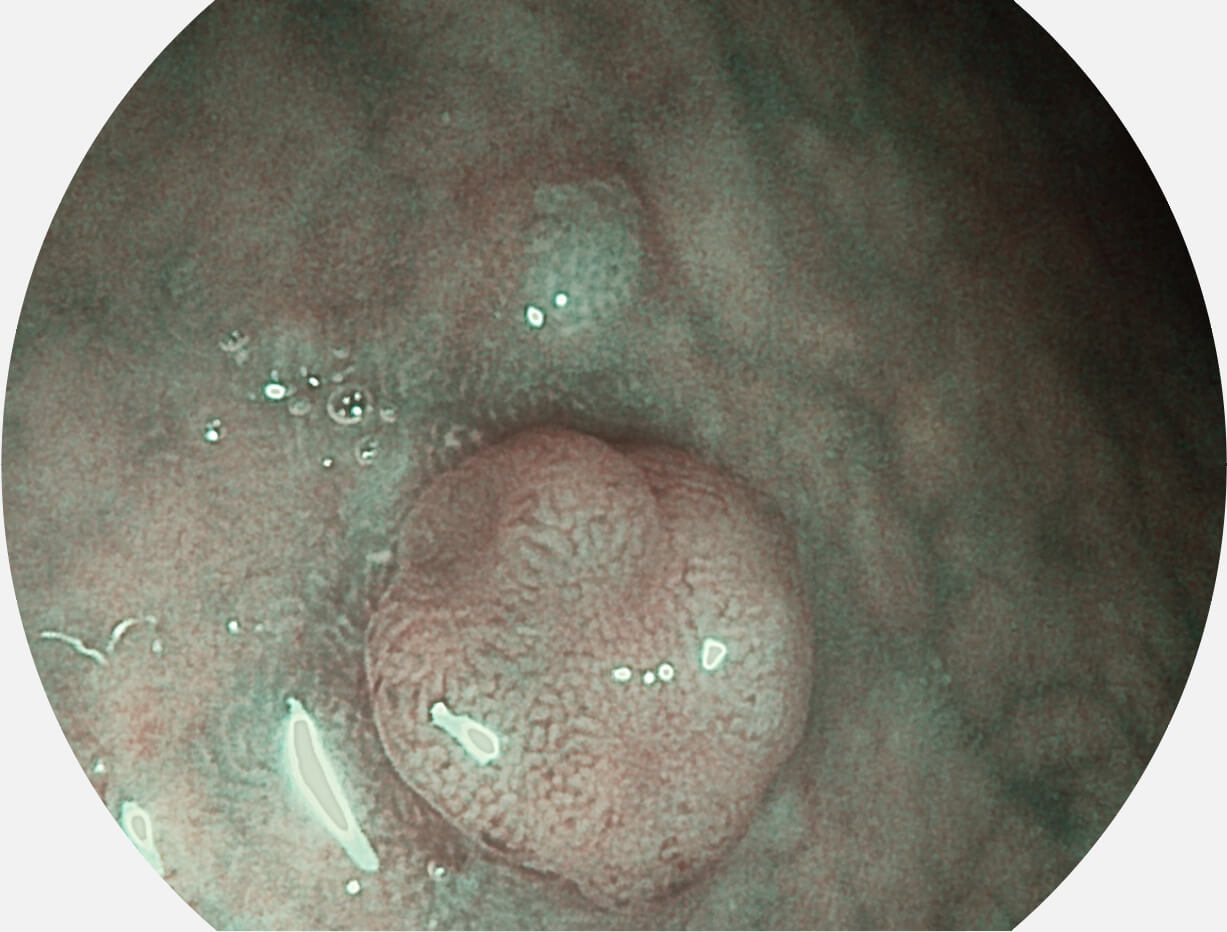

Versatile Intelligent Staining Technology, VIST

强调浅层黏膜结构的同时,保证照明亮度和提升浅层微血管与中层血管颜色对比度,病变边界更清晰。

VIST图像

白光图像